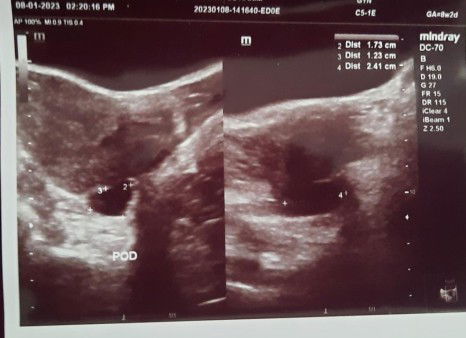

Boleh bantu saya ? Sy last period 11/11/22, bulan 12 takde dtg period pun . upt positive 6/1/23. Pergi scan 8/1/23. Sy jenis period tak teratur. Pergi scan dokter kata tak nampak apa2 lagi. Cuma nampak dinding rahim menebal dan ada fluid kecil tu ta sure apa katanya .. jadi ke pergi scan lg 2 minggu. Adakah ni normal utk yg period tak teratur ? Mohon penjelasan bg sesiapa yg tahu . Sy risau , sampai fikir yg bukan2. #pleasehelp #advicepls #ingintahu